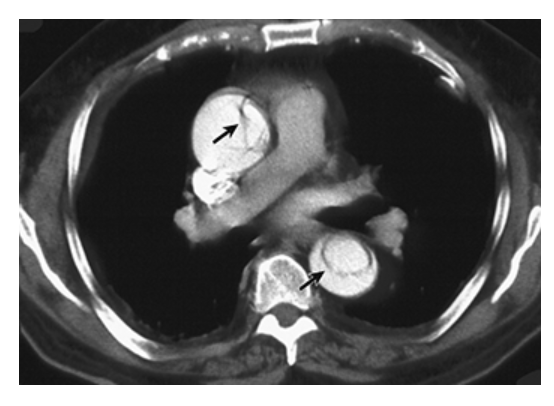

Aberrant Right Subclavian Artery. Axial contrast-enhanced CT shows aberrant right subclavian artery moving toward the right arm crossing the midline of the body (arrow).

Aberrant Right Subclavian Artery. Coronal contrast-enhanced CT shows aberrant right subclavian artery (top arrow). Type B aortic dissection involving the descending thoracic aorta extending up to the left subclavian artery is also seen (bottom arrow).